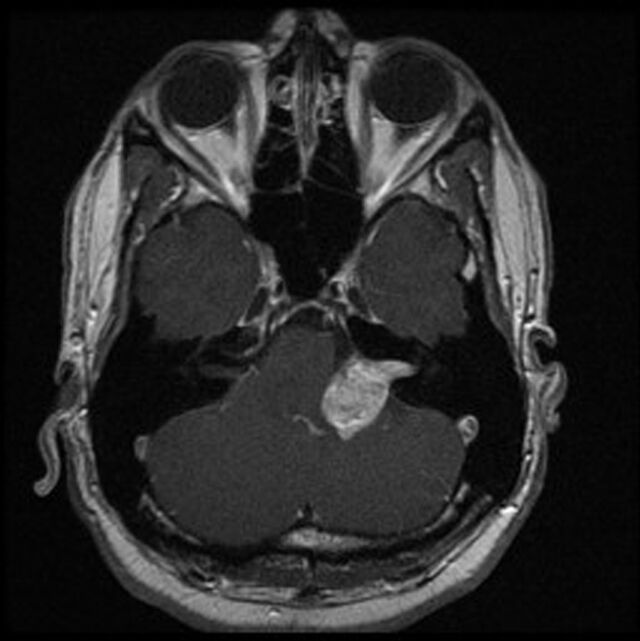

• Das „Akustikusneurinom“ (besser: Vestibularisschwannom, weil es sich fast immer am Gleichgewichtsnerven [Vestibularis] bildet) ist eine gutartige Geschwulst. Sie hat nichts mit Krebs zu tun und bildet keine Tochtergeschwülste (Metastasen).